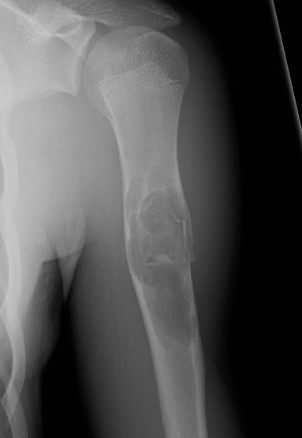

X-ray

Well-defined lucency

- thin sclerotic rim

- usually central

- thinned cortex with slight expansion

- thin internal septa

- can be multi-loculated

Fallen-Leaf (AKA fallen-fragment)

- with pathological fracture

- indicates that the lesion has no matrix and is fluid filled